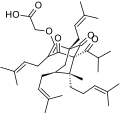

Chemistry

Hyperforin is a prenylated phloroglucinol derivative and is a member of the Polycyclic polyprenylated acylphloroglucinol family, also known as the PPAP family. Hyperforin is a unique PPAP because it consists of a C8 quaternary stereocenter which was a synthetic challenge unlike other PPAP synthetic targets.[3][4][10] The structure of hyperforin was elucidated by a research group from the Shemyakin Institute of Bio-organic Chemistry (USSR Academy of Sciences in Moscow) and published in 1975.[11][12] A total synthesis of the non-natural hyperforin enantiomer was reported in 2010 which required approximately 50 synthetic transformations.[13] In 2010, an enantioselective total synthesis of the correct enantiomer was disclosed. The retrosynthetic analysis was inspired by hyperforin's structural symmetry and biosynthetic pathway. The synthetic route undertaken generated a prostereogenic intermediate which then established the synthetically challenging C8 stereocenter and facilitated the stereochemical outcomes for the remainder of the synthesis.[10]

Hyperforin is unstable in the presence of light and oxygen.[14] Frequent oxidized forms contain a C3 to C9 hemiketal/heterocyclic bridge or will form furan/pyran derivatives.[7][8]

- Natural and semi-synthetic analogues of Hyperforin

-

-

Aristoforin

Aristoforin -

Hyperforin trimethoxybenzoate

Hyperforin trimethoxybenzoate -

Tetrahydrohyperforin

Tetrahydrohyperforin -

Hyperforin nicotinate

Hyperforin nicotinate